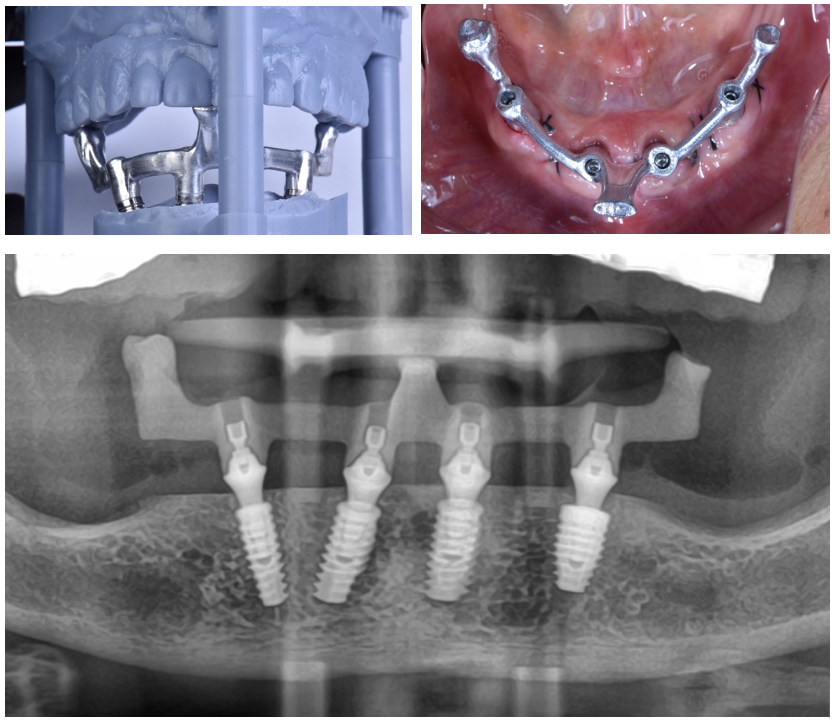

Uma moldagem precisa do implante é a base para a fabricação de uma boa restauração sobre implantes. Portanto, avaliar e garantir a precisão das moldagens é essencial para alcançar resultados clínicos ideais em restaurações implantossuportadas. Atualmente, o uso de scanner intraoral para a transferência dos implantes é uma realidade comum nos consultórios, porém o escaneamento de arcos totais desdentados continua sendo um desafio quanto à precisão.

A precisão das impressões digitais de implantes é um processo multifatorial influenciado por diversas variáveis, incluindo o tipo de scanner usado, a estratégia de escaneamento, a posição, o número e a distância dos implantes, o nível de experiência do operador e o design dos scan bodies usados para transferir a posição dos implantes ou pilares no arco.

Com o escaneamento validado, demos sequência à confecção da prótese protocolo final.

A utilização do escaneamento intraoral na prática clínica torna os procedimentos mais rápidos e mais confortáveis para o paciente, eliminando as etapas de moldagem em um rebordo recém-operado. E os scan bodies de arco total Implacil Osstem facilitaram o escaneamento de arcos totais desdentados, garantindo precisão nos processos.